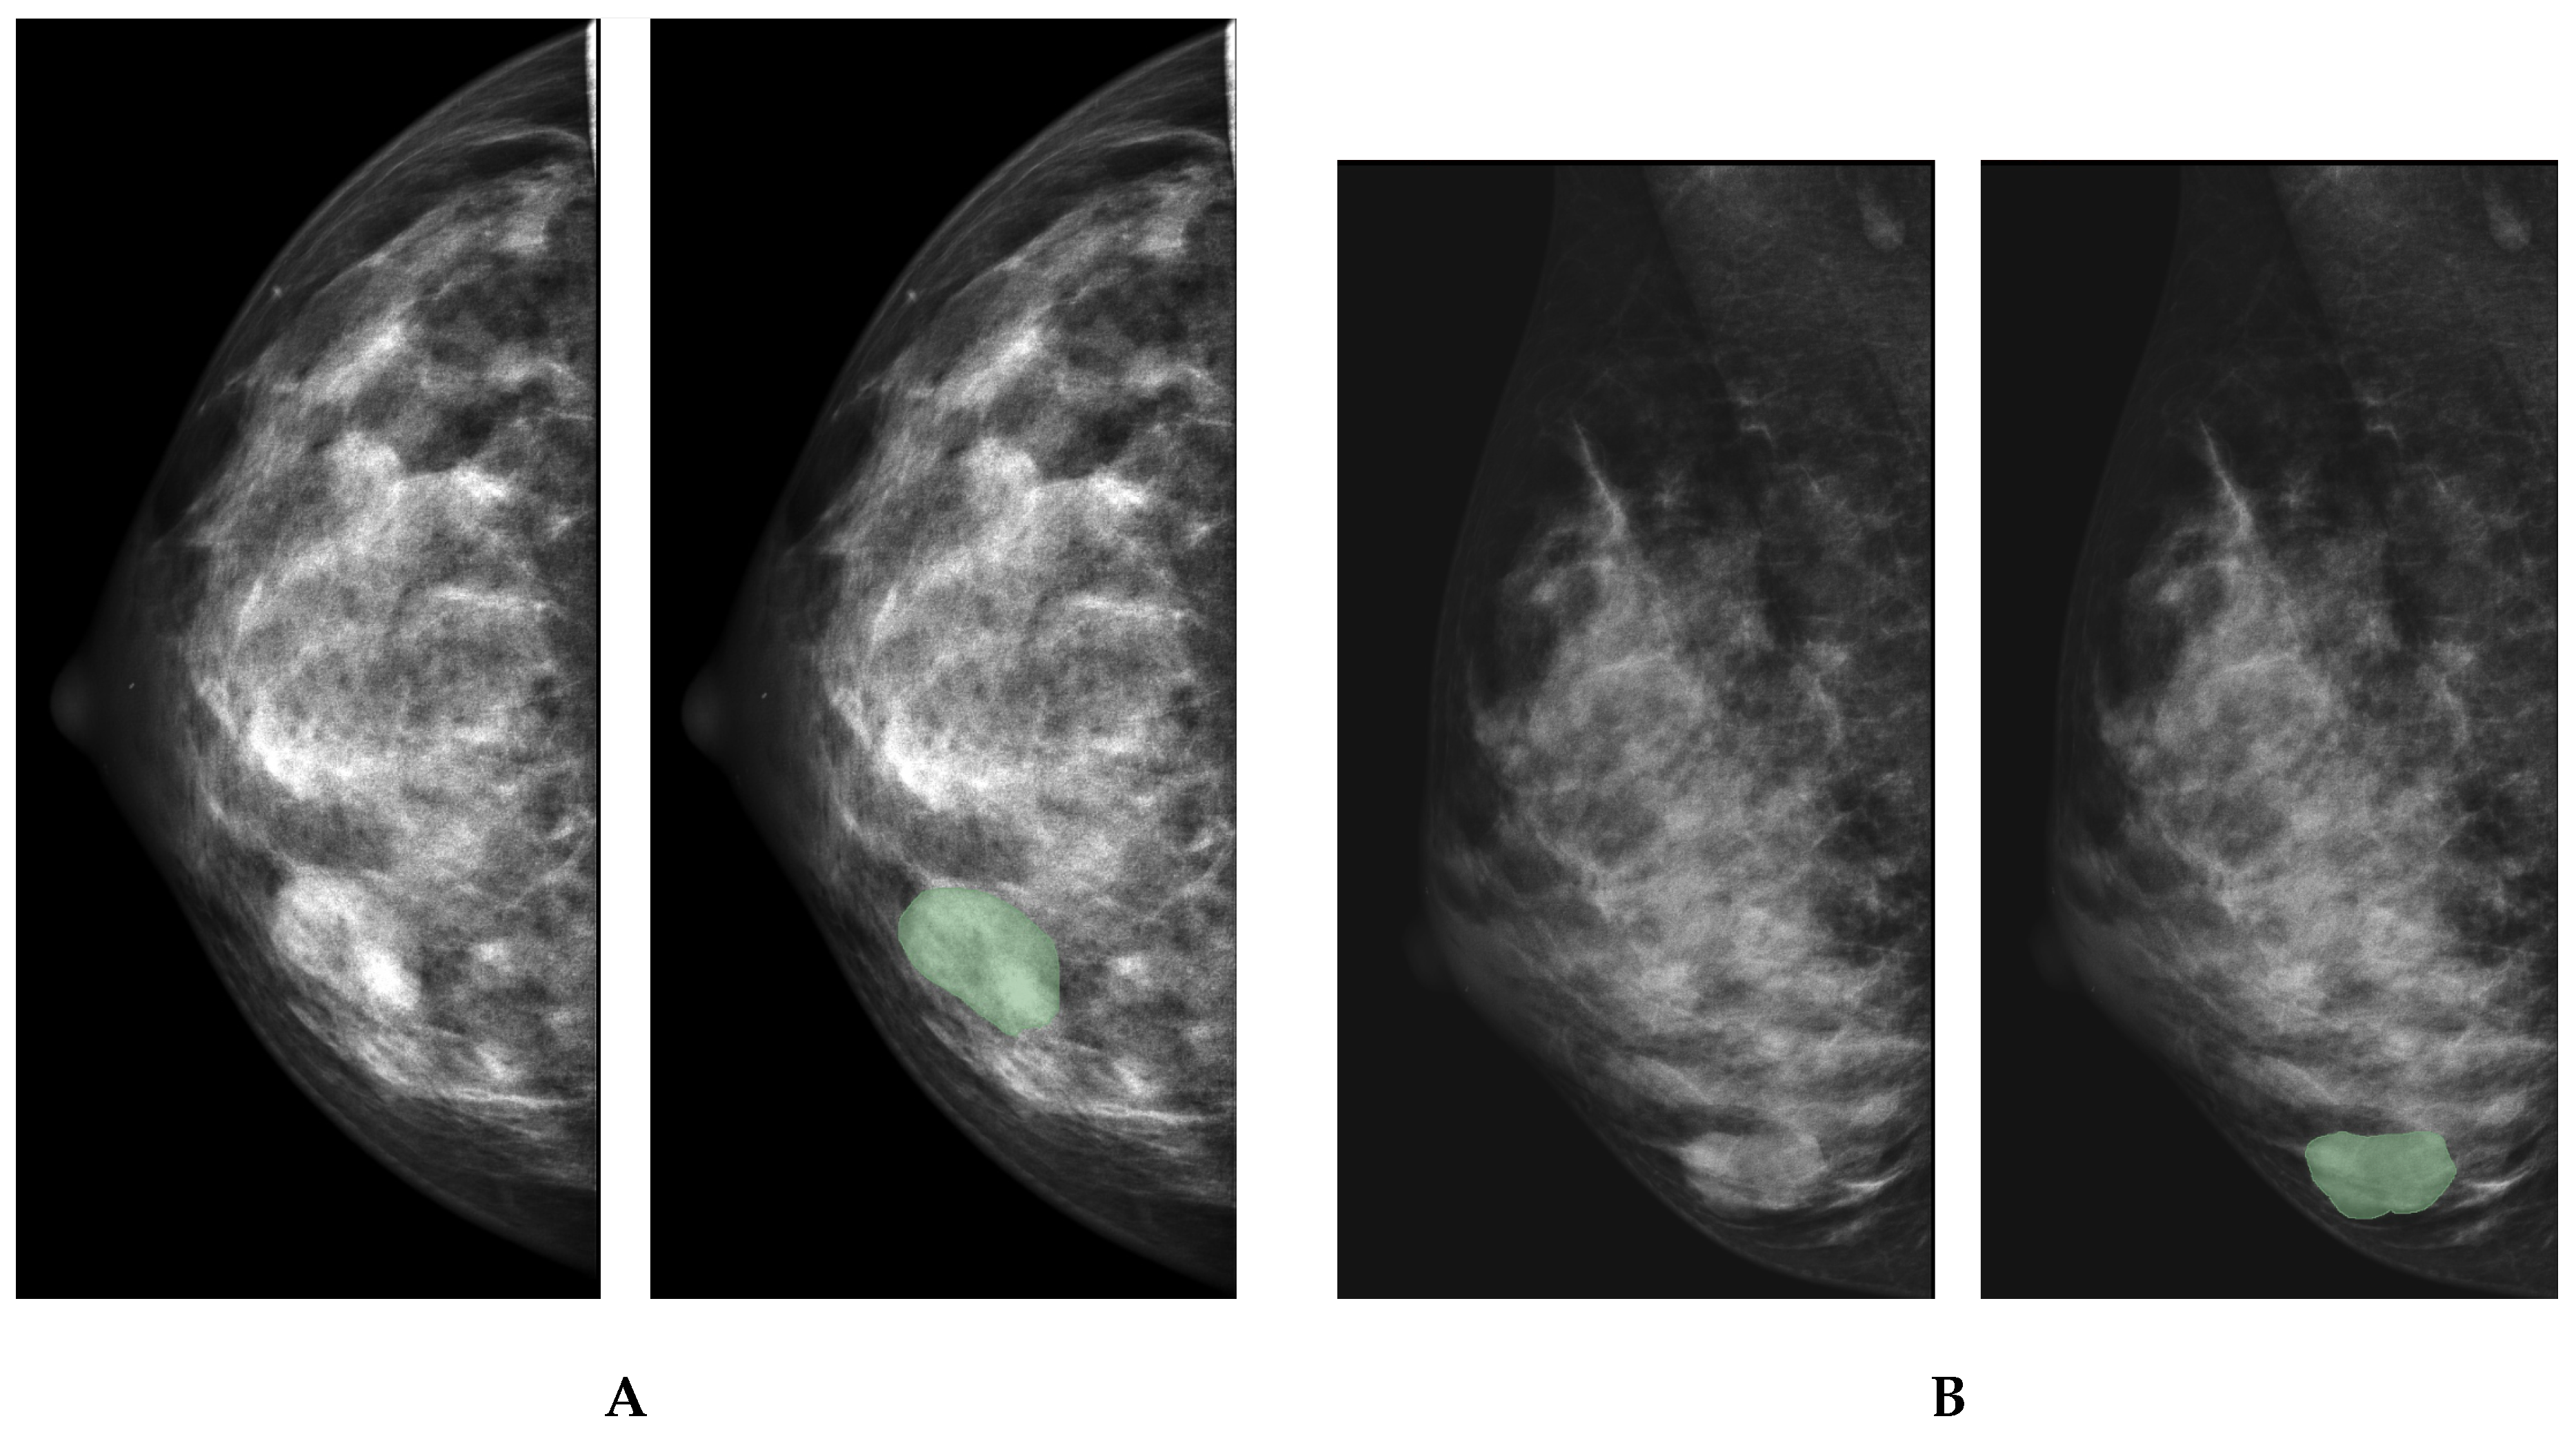

3.2. Data Preprocessing

- Manual segmentation of ROIs is operator-dependent, and it may introduce intra- and inter-observer bias. To minimise the impact of the bias on study findings, our research team comprised two radiologists who delineated ROIs independently. The third radiologist compared segmentation masks and selected the best one for extracting radiomical features within the mask borders. In the future, semi- or fully automatic segmentation with deep learning networks can help us overcome this limitation.